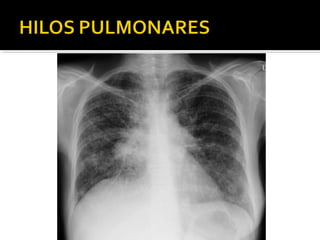

Este documento fornece parâmetros técnicos para realizar uma radiografia de tórax, incluindo posicionamento correto do paciente, dose adequada de radiação e estruturas anatômicas a serem avaliadas, como coração, pulmões, pleura, diafragma e ossos do tórax.